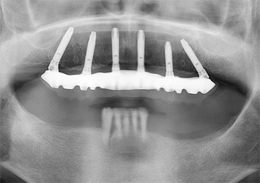

上顎のALL-ON-4①(抜歯即時の症例)

-

- 主訴

- 上の歯が悪くしっかりかめない

- 治療内容

- 上顎右側に残っていた歯の根及び上顎左側に残存していたが、歯周病により動揺があった歯の抜歯を行い、合計6本のインプラントの埋入を行い、ネジ固定式の上部構造を装着した

- 治療費用

- 上顎ALL-ON-4:4,000,000円(税別)

- 治療期間

- 6ヶ月